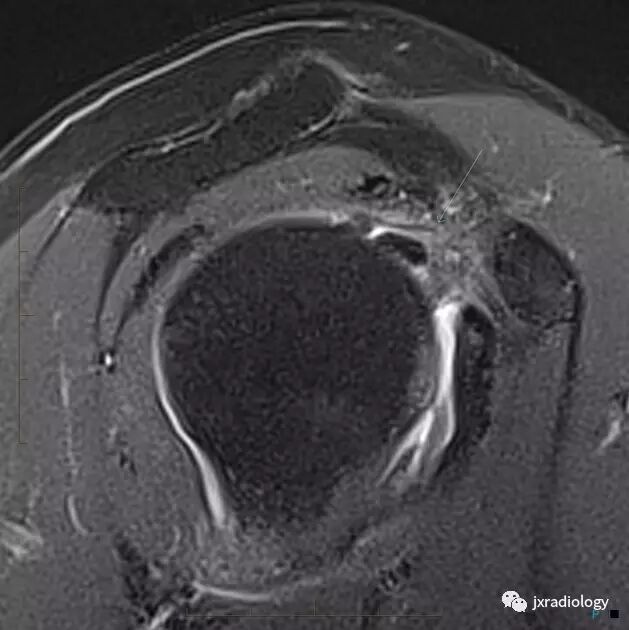

肩袖间隙异常软组织信号(细箭)

腋囊增厚和水肿(细箭)

腋囊增厚纤维化(T1/T2均为低信号):

• 正常下盂肱韧带测量值<4毫米,在斜冠位上关节囊中间层面显示最好;在粘连性关节囊炎患者中,腋隐窝软组织增厚≥1.3厘米

• 关节囊增厚

• 肩袖间隙异常软组织增厚伴信号异常

• 增强后腋隐窝和肩袖间隙的关节囊或滑囊强化